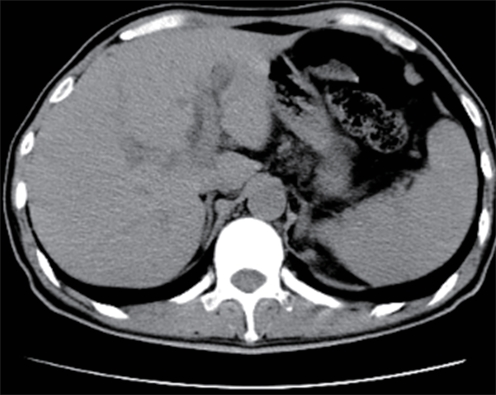

基于CT图像的腹部肌肉内部分层分析对原位肝移植术后并发症的预测价值

石鑫, 梁重霄, 张蓓, 王继萍

2025, 41(2): 314-321. DOI: 10.12449/JCH250218

摘要(706) HTML (336) PDF (3265KB)(40)

摘要:

目的  本文旨在肌肉脂肪浸润的基础上,利用分层分析的方法将肌肉内部按照不同的密度范围划分成不同的亚分区,进一步研究肌肉密度改变对原位肝移植术(OLT)后并发症(Clavien-Dindo≥Ⅲ)的影响。  方法  回顾性分析2013年5月—2020年9月于吉林大学第一医院行OLT的145例患者,以患者腰3椎体水平最大层面的CT平扫图像作为原始数据,利用Neusoft Fatanalysis软件对图像进行相关肌肉参数的测量。符合正态分布的计量资料组间比较采用成组t检验;不符合正态分布的组间比较采用Mann-Whitney U秩和检验。计数资料组间比较采用χ2或Fisher检验。利用RIAS软件进行临床特征提取及分析建模,分别建立逻辑回归(LR)、支持向量机(SVM)、随机森林(RFC)3种机器学习模型,并绘制不同模型的受试者操作特征曲线(ROC曲线)、校正曲线、决策分析曲线,计算ROC曲线下面积(AUC)、灵敏度、特异度、精确率、F1分数、准确率。  结果  采用肌肉分层分析前的7种临床特征建立LR-C、SVM-C、RFC-C 3种机器学习模型,其中RFC-C模型测试集的AUC值为0.803、灵敏度0.588,特异度0.778。采用肌肉分层分析后的16种临床特征建立的LR-CS、SVM-CS、RFC-CS模型中,LR-CS及SVM-CS模型测试集的AUC值较高,均为0.852,灵敏度分别为0.765、0.706,特异度分别为0.889、0.926,通过对比肌肉分层分析前后各模型测试集的AUC、灵敏度、特异度、精确率、F1分数、准确率后发现,肌肉分层分析后预测模型的参数均有所提升。通过对比各预测模型的决策分析曲线和校正曲线,发现LR-CS及SVM-CS模型对于预测OLT患者术后并发症(Clavien-Dindo≥Ⅲ)具有良好效能。  结论  在肌肉脂肪浸润的基础上,利用分层分析的方法将肌肉内部按照不同的密度划分成不同子区,对于OLT患者术后并发症有一定预测价值。